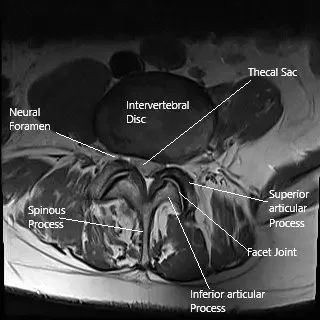

La cirugía láser de columna puede utilizarse para tratar una hernia de disco intervertebral, como se observa en esta sección de resonancia axial de la columna lumbar.

La columna vertebral está formada por vértebras separadas por discos intervertebrales. Estos discos actúan como cojines, permitiendo que la columna absorba los impactos y mantenga la flexibilidad. Cuando un disco se abulta o se rompe, puede presionar contra la médula espinal o los nervios, causando dolor, debilidad y entumecimiento. La cirugía láser de columna se centra en la zona problemática, normalmente una hernia discal, para aliviar la presión sobre los nervios y aliviar los síntomas.